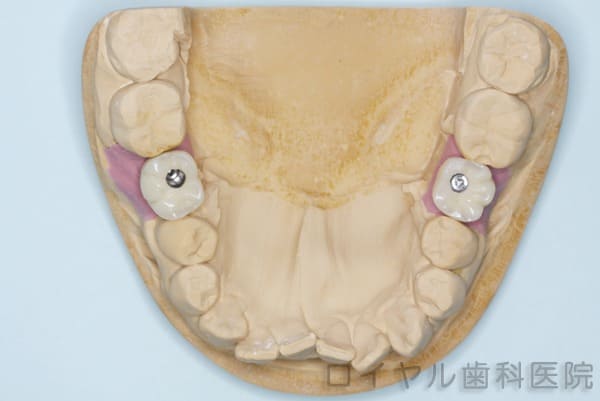

模型作成

-

被せ物はこういう形でできあがってきます。